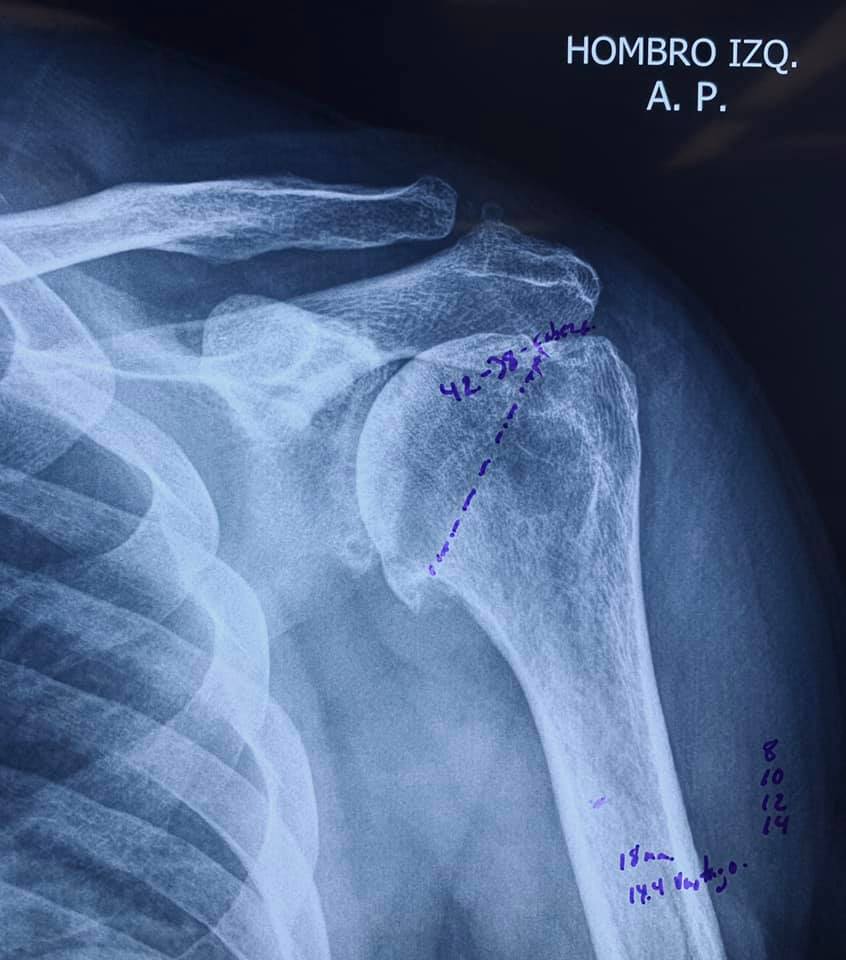

Artroplastia de anatomía inversa de hombro, en la enfermedad articular degenerativa glenohumeral avanzada. Joya de la ingeniería biomédica. Tomando las medidas de protección quirúrgica.